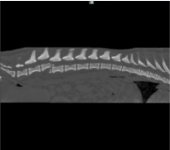

Kochany, radosny piesek.. Taka była Nora. Dwa tygodnie temu.,zrobiła o krok za daleko, w kilka sekund uciekła przez uchyloną przez listonosza furtkę. To naprawdę były sekundy. Moją małą kruszynke potracił samochód. Nora ma uszkodzony rdzeń kregowy, zmiany na nerkach,słaba widoczność pęcherza moczowego, stan zapalny w organizmie. Stan Nory był bardzo zły ale nie pozwoliliśmy jej uśpić .Ten piesek na to nie zasłużył!! Proszę pomóżcie uratować mojego pieska ,który jest dla mnie wszystkim!!!! Moja kochana perełka przeżyła bardzo skomplikowaną operację. Od przyszłego tygodnia zaczynamy rehablitacje Nory. Będziemy jeździć 3 razy w tygodniu na zabiegi i do Pani doktor. Pani doktor powiedziała że zrobiła wszystko co w jej mocy ,ustabilizowała nozki. Nora ma uszkodzony rdzeń kregowy. Pani doktor wysunęła 4 kręg w górę (żeby była ruchomośc)I nałożyła na 5 cement . Nora nie ma czucia w nóżkach, ale będziemy uczyć ja tzw,,chodu rdzeniowego". Nora podnosi głowę do góry,siada,widzi,słyszy,reaguje na imię. W przyszłym tygodniu zaczynamy rehablitacje,czym wcześniej zaczniemy tym lepiej . Na rehablitacje będziemy jeździć 3 razy w tygodniu do kliniki doktora Grzegorza Wąsiatycza w Poznaniu .Za dwa tygodnie,jak Nora nie będzie miała już szwów, to zaczniemy działać na bieżni mokrej . Czy Nora będzie chodzić? Zadaje codziennie ,po kilkanaście razy to pytanie lekarzowi ,chirurgowi, technikowi..odpowiedz zawsze jest ta sama . Czas pokaże... Wszystko zależy od organizmu, od tego jak będziemy ja rehablitować. Ja wierzę... Oczywiście że tak. Błagam o pomoc w uzbieraniu pieniążków na rehabilitację, pomóżcie mojej perełce uzbierać chociaż na jedną wizytę rehabitacyjna.